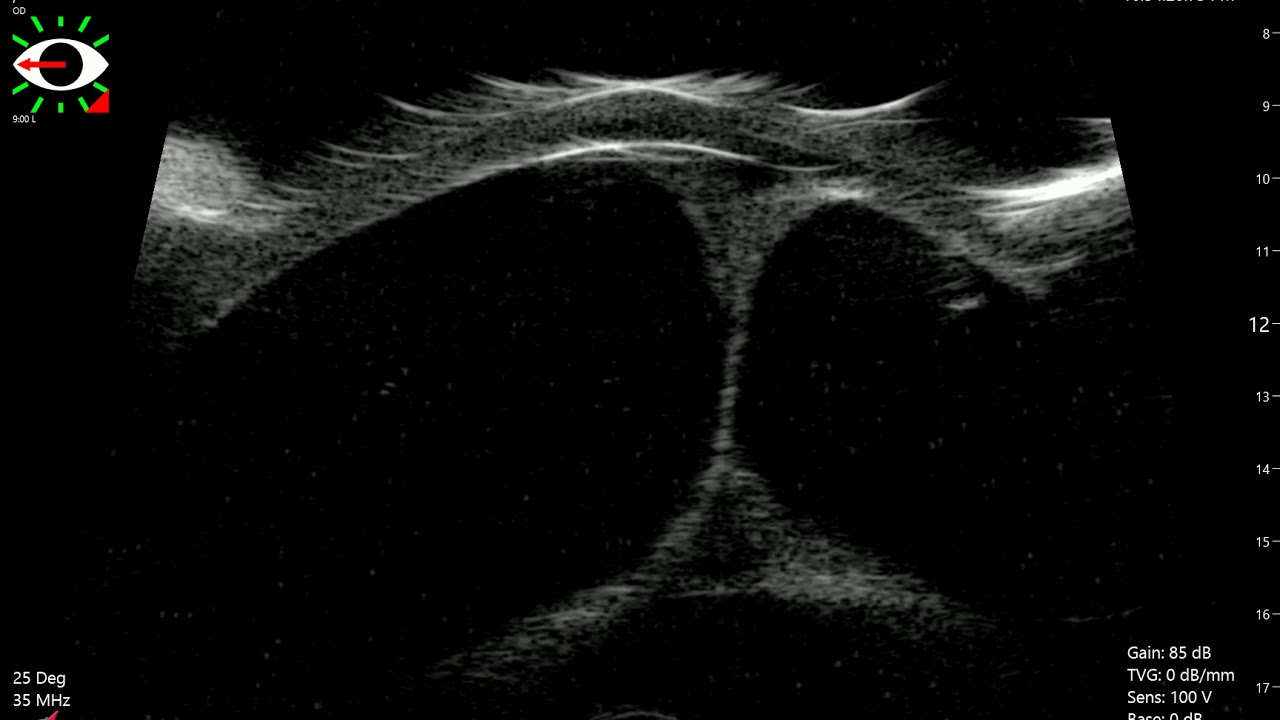

From www.ophthalmologyglaucoma.org

Ultrasound Biomicroscopy in an Eye with Iris Bombe Ophthalmology Iris Bombe Definition A condition occurring in posterior annular synechia in which an increase of aqueous humour contained in the posterior chamber causes a forward. Learn about its symptoms, treatment and surgical options from columbia. The meaning of iris bombé is a condition in which the iris is bowed forward by an accumulation of fluid between the iris and the. Iris bombe is. Iris Bombe Definition.

【臨床】UBM for iris bombe a cat by NCHU Ophthalmology Taiwan YouTube Iris Bombe Definition Iris bombe is a condition in which the iris touches the lens or vitreous, causing angle closure glaucoma. Four glaucoma surgeons discuss the possible causes, diagnosis,. Learn about its symptoms, treatment and surgical options from columbia. Iris bombé is a condition where the iris is pushed forward by aqueous trapped in the posterior chamber, causing angle closure and. The meaning. Iris Bombe Definition.